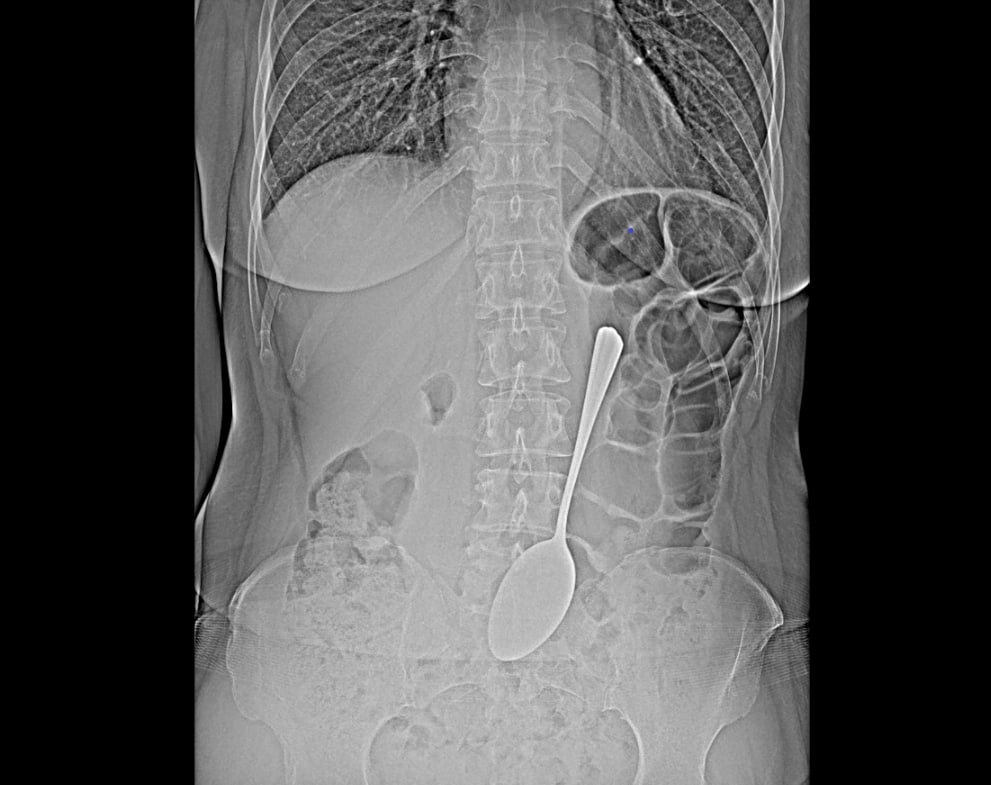

Врачи-эндоскописты БСМП им.В.В.Ангапова извлекли из желудка обычной женщины обычную столовую ложку длиной 18 см. Предмет достали из желудка с помощью эндоскопа и соответствующих инструментов, что помогло избежать сложной хирургической операции.

- Инородные предметы в желудке могут спровоцировать перфорацию желудка, кишечную непроходимость. Если мелкие предметы вроде монет могут выйти из организма самостоятельно, то в случае со столовой ложкой все могло быть серьезнее, - комментирует врач-эндоскопист РК БСМП им.В.В.Ангапова Бабудоржиева Валентина Владимировна.